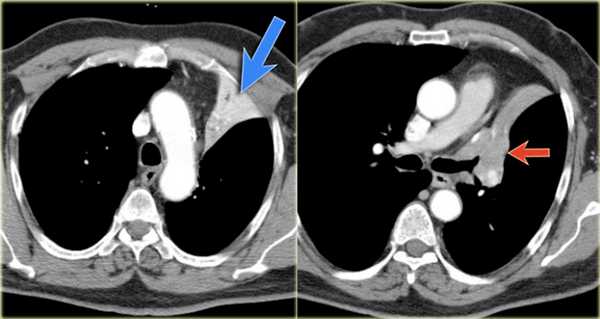

Ателектаз нижней доли левого легкого

На рентгенограмме визуализируются изменения трехгранной формы высокой плотности, расположенные позади тени сердца, что хорошо выявляется на боковом снимке. На боковом снимке при оценке контура диафрагмы спереди назад определяется все менее четко. Исходя из названия раздела напрашивается диагноз — ателектаз нижней доли левого легкого. В норме прозрачность легкого внизу выше, а в нашем случае наоборот (синяя стрелка).

На ниже представленной рентгенограмме пациента с карциноматозом плевры левое легкое полностью компрессируется плевральной жидкостью (левый гемоторакс). В выше представленных случаях был обтурационный ателектаз, а в этом компрессионный, что лучше визуализируется на КТ (синяя стрелка). КТ данному пациенту также проводили по причине легочного эмболизма (красная стрелка).